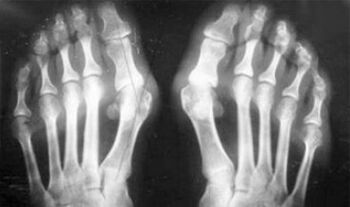

- Metabolismoa urratzea (gout).

Ikus dezakezuenez, sintomen desberdintasunak hutsalak dira: bi kasuetan mina, zurruntasuna eta nekea daude. Artritisak eta artrosiak artikulazio desberdinetan eragina izan dezakete giza gorputzean. Bizkarrezurrean eta disko intervertebraletan kalteak eginez, osteokondrosia garatzen da - artrosiaren antzekoa da. Gaixotasunaren lekuaren arabera, orkatilaren artrosiaren, sorbalda, hip junturen eta abar bereizten da.